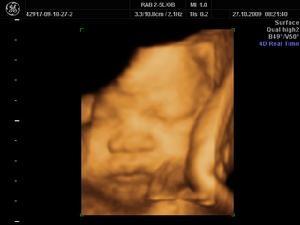

四维彩超是超声检查的一种,但是和其他超声波检查相比,四维彩超则可以除了一般彩超的功能外,最重要的是能进行胎儿头部立体成像,可清晰地显示眼睛嘴巴鼻子耳朵等器官,也可观察胎儿的运动等状态以判断胎儿是否健康 ...

四维彩超是超声检查的一种,但是和其他超声波检查相比,四维彩超则可以除了一般彩超的功能外,最重要的是能进行胎儿头部立体成像,可清晰地显示眼睛嘴巴鼻子耳朵等器官,也可观察胎儿的运动等状态以判断胎儿是否健康。同样四维彩超相比其他检测更能有判断宝宝的性别。虽然在检查过程中,医生会尽量避开宝宝的性别特征,但是四维彩超检查单里的小数据则是耐人寻味,今天艾卫宝德的小编特地为各位孕妈准备了四维彩超解密大全,大家一起期待好“孕”到来。